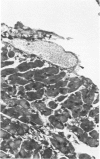

In male BALB/c mice aged 5-6 weeks inoculated three times at intervals of 15 days with 1 X 10(7) epimastigote forms of the PF strain of Trypanosoma cruzi and challenged 30 days after the last inoculation with 2 X 10(4) trypomastigote forms of the Colombia strain of T cruzi (the mice were sacrificed 80-100 days after the challenge) a cardiomyopathy very similar to that observed in the chronic phase of Chagas' disease in man develops. The cardiac syndrome is characterized grossly by cardiomegaly with hypertrophy, dilatation of ventricular chambers, and thinning of the apex of the left ventricle (apical aneurysm) and microscopically by focal areas of myocytolytic necrosis and myocardial degeneration with an inflammatory response composed of mononuclear cells (predominantly macrophages and a few lymphocytes) with concurrent interstitial fibrosis and occasional myofibers containing pseudocysts. In addition, aggregated platelets and occlusive thrombi were found in small epicardial and intramyocardial vessels of infected mice as compared with controls. The potential role of intravascular platelet aggregation in the causation of focal myocardial necrosis and degeneration and apical aneurysm in experimental T cruzi cardiomyopathy in BALB/c mice is discussed.